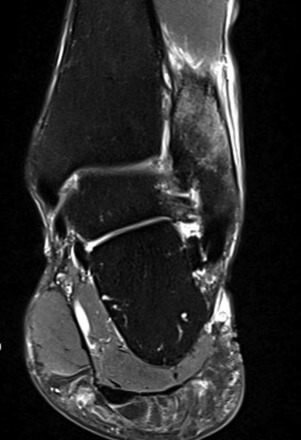

Vor der Behandlung zeigte der AOFAS Score 40 Punkte, nach drei Behandlungen lag der Score bei 70 und nach fünf Behandlungen ermittelten wir einen Wert von 100. Somit war der Wert eines gesunden Sprunggelenkes erreicht. Zur Ermittlung der Schwellung haben wir den Umfang an der Fibulaspitze im Seitenvergleich gemessen, der vor der Behandlung an der frakturierten Fibula um ca. 10% größer war als auf der Gegenseite. Nach den ersten drei Behandlungen waren die Umfänge im gleichen Bereich identisch. Die anfänglich deutlich limitierte Dorsalextension sowie Hebung des Fußaußenrandes des betroffenen Sprunggelenkes war nach der gesamten Therapie wieder seitengleich normwertig. Der anfänglich intensive Klopfschmerz wurde bereits nach der zweiten Behandlung nicht mehr angegeben. Auch das alltägliche Schmerzlevel verringerte sich nach jeder Behandlung deutlich, sodass bereits nach drei Behandlungen mittels ESWT sowohl mit als auch ohne Orthese kaum noch Schmerzen vorhanden waren und bereits eine Schrittzahl von ca 10.000 am Tag möglich war. Radfahren war ab der 3. Behandlungswoche erlaubt und der Patientin beschwerdefrei möglich. Nach drei Behandlungen (ab der 4. Woche) wurde bereits von der Stabilorthese auf den elastischen Anteil reduziert. Im Rahmen der Trainingstherapie wurden ab der 4. Wochen schon kurze Läufe (10- 15 Min.) auf dem Laufband begonnen, die ebenfalls beschwerdefrei toleriert wurden. Am Ende der Behandlung legte die Patientin bereits 15.000 Schritte am Tag zurück. Ein zwischenzeitlich durchgeführtes Kontroll-Röntgenbild zeigte keine sekundäre Dislokation. Die sechs Wochen nach Beginn der Therapie durchgeführte MRT zeigte eine nahezu vollständige Konsolidierung des Knochens (vgl. Abb. 3 und Abb. 4).

Abbildung 4. Sagittales Schnittbild (sag/pd).